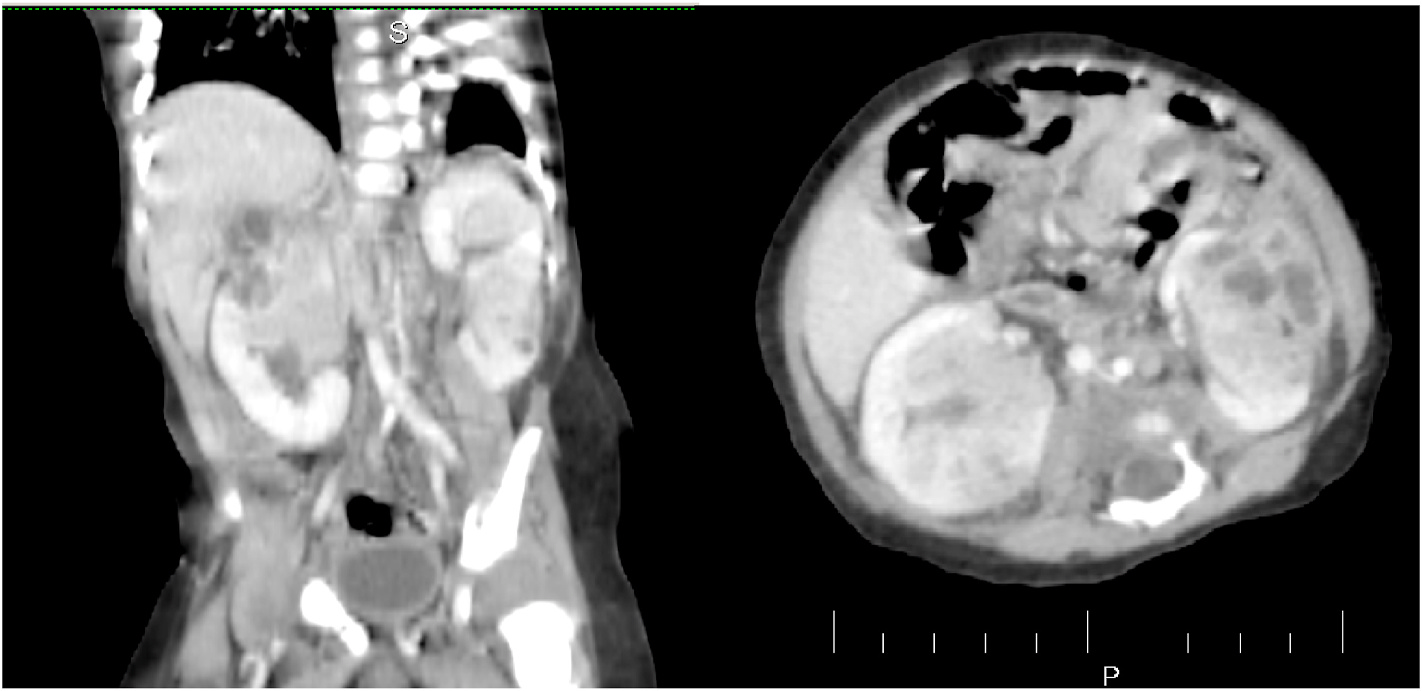

We received a referral from a pediatrician regarding a 3-month-old baby who had an incidental discovery of masses in both kidneys during an ultrasound examination. A follow-up CT scan without contrast indicated the presence of nephroblastoma/Wilms tumor. The infant had experienced a fever two weeks prior, for which the local general practitioner provided partial treatment with antibiotics. Currently, the baby is not running a fever and is fussy but able to consume food orally. There is no family history of cancer, and apart from a palpable non-tender mass in the left kidney, the physical examination did not reveal any noteworthy findings. Further investigations were conducted, revealing a total leukocyte count of 18,600 with 51% neutrophils, a hemoglobin level of 10.8, and a C-reactive protein level of 17.4. Other tests yielded normal results, including negative findings for growth in blood and urine cultures. Subsequently, a CT scan with contrast was performed, confirming the presence of nephroblastoma/Wilms tumor as the differential diagnosis (Figure).

Computed tomography (CT) is considered to be the most sensitive and accurate imaging modality for the diagnosis of ALN. CT scan with IV contrast has got better anatomical delineation providing more information on the lesion aspects, which goes in favor of ALN. The lesion presents as focal or global enlargement of the kidney. The corticomedullary differentiation is essentially blunted by edema with calyceal effacement.